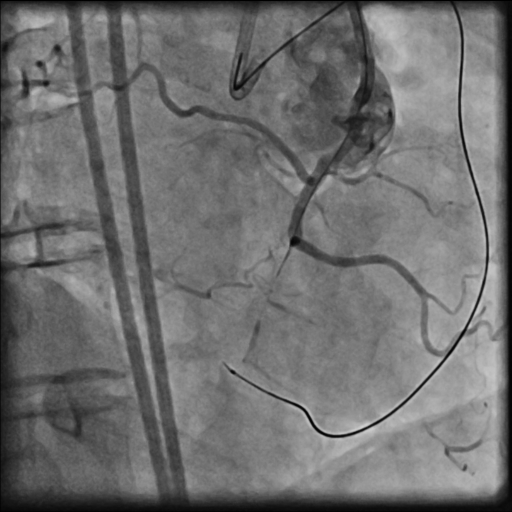

LMCA was engaged with JL 4.0 7 Fr. catheter. First septal collateral was used to reach the distal cap of the lesion using Sion black, Runthrough extrafloppy and Fielder XT-R wire with microcatheter but could not penetrate the distal cap. The lesion could not be crossed with Gaia second and Gladius¢ç Mongo¢ç wire. Antegrade approach was decided to a cross the lesion with Gaia second wire. Antegrade approach caused a dissection resulting in a sub intimal hematoma which extended into the Posterolateral branch. This dissection and the hematoma straightened the vessel near the distal cap. Now this straightening allowed the ASAHI Gladius¢ç Mongo¢ç wire to cross the distal cap retrogradely. The Gladius¢ç Mongo¢ç wire could not be positioned into the true lumen. Now to avoid further dissection proximally the Mongo wire was exchanged with Pilot 150 wire. This wire could cross the proximal cap and finally into the guide catheter. Pilot 150 wire was exchanged with Choice Floppy LS 300 cm which was externalized. A finecross microcatheter was advanced over this wire antegradely. Retrograde microcatheter removed and rest of the case was completed via antegrade approach over Runthrough NS Floppy wire. Lesion was predilated with 2.5x12 mm NC balloon @ 12 atm. Promus Elite 2.75x38 mm DES deployed in mid to distal RCA @ 12 atm. An overlapping stent Xience Xpedition 3.0x28 mm DES deployed from ostium to mid RCA @ 11 atm. Post dilatation with 3.25x10 mm NC balloon @ 11 atm. Distal TIMI III flow achieved.

PTCA 1.mp4